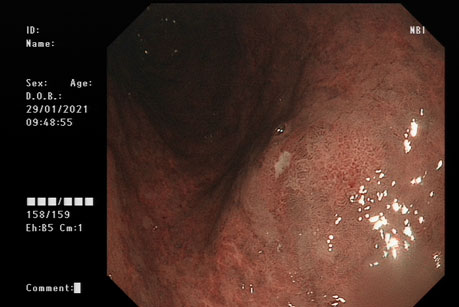

内镜下观察病变的范围